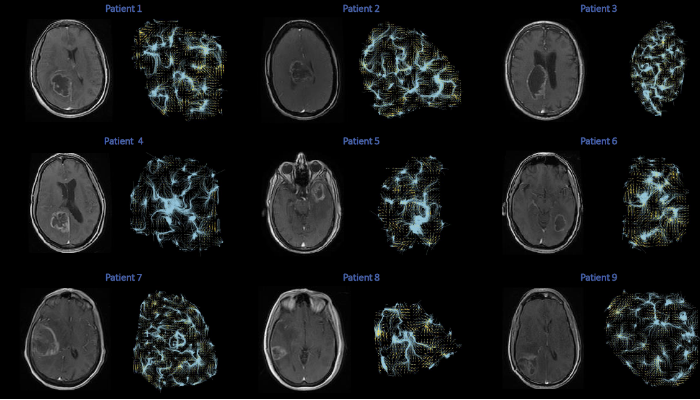

Clinical context of proposed research: Patients with treatment (medication) resistant epilepsy can become candidates for surgical ablation of the epileptic foci. To determine which region of the brain is the source of the seizures patient undergo phase-I and if necessary phase-II epilepsy monitoring. Phase-I requires non-invasive electroencephalographic recordings using electrodes placed on the patient’s scalp. If these recordings are inconclusive, patient become candidates for intracranial depth electrode mapping, which requires brain surgery to place the depth electrodes (e.g., see Fig. 1) as shown in Fig. 2. An alternative depth electrode that is used for clinical purposes is AdTech’s “All-in-one Macro-Micro” electrode, where the micro contacts are radially spaced on the body of the depth electrode. These electrodes are FDA approved for standard-of-care use side-by-side with clinical research recordings. These electrodes and this procedure are the platform for the recordings we propose here. Importantly, we will only perform research recordings from sites that will necessarily be damaged by the clinical procedures, and due to the unknown epileptic foci will later be deemed either healthy or epileptic tissue.

Background to electrochemical measurement approach. The critical measurement approach that enables simultaneous electrochemical detection of dopamine, serotonin, and norepinephrine is an electrochemical method called “fast scan cyclic voltammetry”. This approach has been utilized in rodents and rodent brain tissue for over 25 years. Briefly, a voltage is applied to a carbon fiber microelectrode. If this voltage is greater than or equal to the oxidation potential of a chemical species, then an electrochemical oxidation reaction takes place and the transfer of electrons (to the carbon fiber) is measured as a change in current. By quickly scanning over a range of applied potentials (e.g., -0.6V to +1.4V and back to -0.6V at a scan rate of 400V/s), a range of electrochemical currents can be detected. We have developed a machine learning based algorithm that allows us to infer the chemical species’ identity and concentration from this induced electrochemical spectrum. Tests like those shown in Figure 3 demonstrate that we can continuously monitor dopamine, serotonin, and norepinephrine micro-fluctuations with 100ms temporal resolution, which is orders of magnitude faster and with direct chemical specificity better that existing non-invasive measurement modalities like fMRI and PET and invasive approaches like microdialysis.